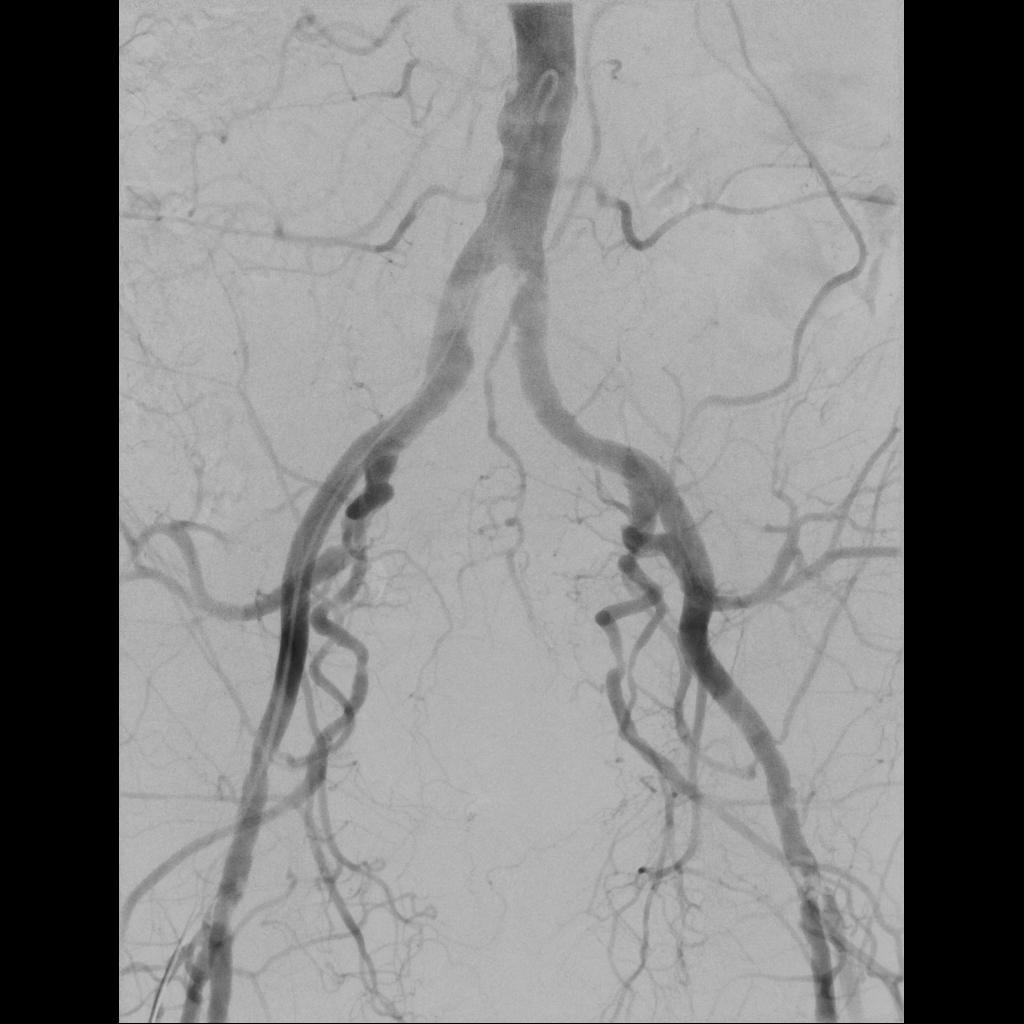

In der interventionellen Radiologie beschränkt sich die Tätigkeit des Radiologen nicht allein auf die bildgebende Diagnostik. Vielmehr übernimmt er eigenständig minimalinvasive Eingriffe und trägt dabei die Verantwortung für die prä-, peri- und postoperative Versorgung der Patient: innen.